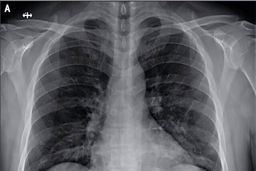

کرونا چه بلایی بر سر ریهها میآورد؟

خبرمهم: کروناویروس به خاطر وجود شاخکهای تاجی شکلی که بر روی سطوحش وجود دارد، با این نام شناخته شده و میتواند سبب…